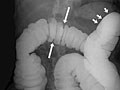

• In a double-contrast or air-contrast study, the colon is first filled with barium, and then the barium is drained out. This leaves only a thin layer of barium on the wall of the colon. The colon is then filled with air. This provides a detailed view of the inner surface of the colon. It makes it easier to see narrowed areas (strictures), diverticula, and swelling.

• Find problems with the structure of the large intestine. Problems may include narrowed areas (strictures) or pockets or sacs (diverticula) in the intestinal wall.

• A narrowing (stricture) in the bowel.

• Polyps or growths on the inner wall of the colon.

• Sacs in the colon wall (diverticulosis).